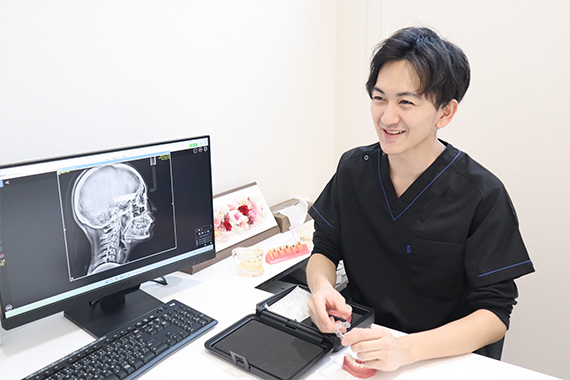

学会認定医

監修

日本矯正歯科学会認定医監修

お子さまの成長に寄り添う

矯正治療をご提供

お子さまの矯正治療は、顎や歯の成長段階をしっかり見極めながら進めることが大切です。当院では、日本矯正歯科学会認定医の監修のもと、お子さまの成長に合わせた矯正治療をご提案しています。ご家族のかたと一緒に不安や疑問を共有しながら、無理のない治療計画を立て、安心して進められる環境作りを大切にしています。

01 初診無料相談

日本矯正歯科学会認定医の監修のもと、お子さまの歯並びや噛み合わせを丁寧に確認し、矯正が必要かどうか、いつから始めるのが適しているかをわかりやすくご説明します。治療内容や期間、費用についても事前にしっかりお話ししますので、矯正治療を検討されている保護者のかたも安心してご相談いただけます。

02 精密検査

歯科用CTや口腔内スキャナー(iTero)を使用して、お子さまのお口の状態を立体的かつ詳細に分析します。顎の成長や歯の動きも予測し、検査結果をもとに一人ひとりに適した治療計画をご提案します。